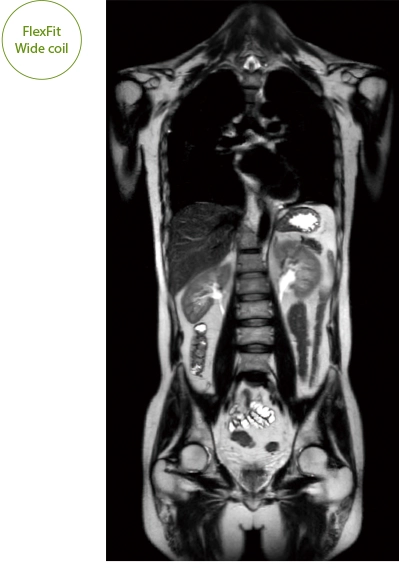

The ECHELON Synergy ZeroHelium is equipped with a flexible head and neck coil that allows one-action setup via sliding installation, as well as a Flex coil that provides wide and flexible coverage of the imaging area. This enables flexible adaptation to different part of body.

It can also be used with time-consuming scans such as Whole Body DWI and Whole Spine imaging, providing more detailed information in many areas than previously possible.